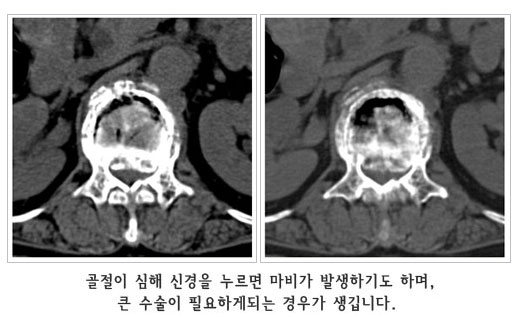

°ñ´Ù°øÁõÀº ¾à¹°Ä¡·á, ¿îµ¿ ¹× ½ÄÀÌ¿ä¹ýµîÀÇ º¸Á¸Àû Ä¡·á·Î ´ëºÎºÐ Àß ÇØ°áµÉ ¼ö ÀÖ½À´Ï´Ù. °ñÀýÀÌ »ý±ä °æ¿ì´Â ¾ÈÁ¤°ú º¸Á¶±â µîÀ¸·Î Ä¡·áÇÏÁö¸¸ ¼ö¼úÀû Ä¡·á°¡ ÇÊ¿äÇϱ⵵ ÇÕ´Ï´Ù. ôÃß°ñÀýÀÇ °æ¿ì¿¡´Â ÇǺÎÀý°³¸¦ ÇÏÁö¾Ê´Â ÃÖ¼Ò Ä§½ÀÀû ½Ã¼úÀÌ ÀÌ¿ëµË´Ï´Ù. ±×·¯¹Ç·Î Á¶±â¿¡ Ä¡·á ¹× ¿¹¹æÀ» öÀúÈ÷ ÇÏ´Â °ÍÀÌ Áß¿äÇÕ´Ï´Ù.